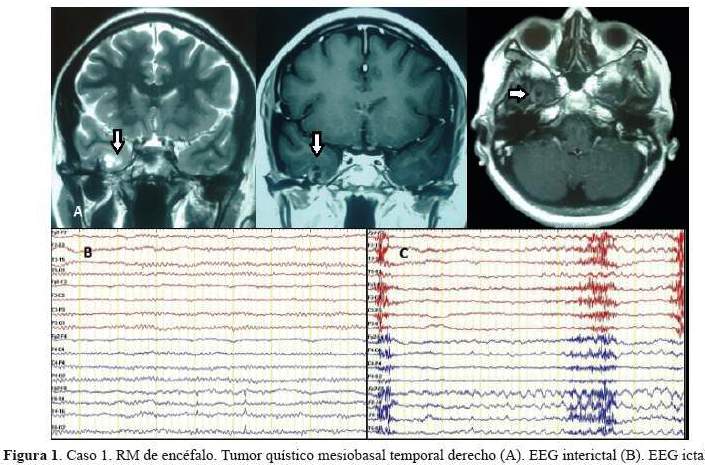

De los 5 casos, 3 cirugías correspondieron a pacientes con epilepsia temporal mesial derecha (2 por esclerosis mesial temporal y 1 por ganglioglioma mediobasal temporal anterior) y 2 correspondieron a patología dual (1 con EMT derecha más lesión gliótica cicatrizal de un angioma cavernoso temporal neocorical ipsilateral operado previamente y 1 con EMT izquierda más gliosis frontal ipsilateral). De los 3 pacientes con epilepsia temporal mesial derecha, 2 sólo requirieron de estudios paraclínicos en fase 1: EEG/VideoEEG y RM encéfalo estructural y 1 requirió además de PET interictal (fase 2), pues a pesar de que la semiología y actividad electrográfica ictal correspondían a una epilepsia del lóbulo temporal mesial derecho, la RM de encéfalo dejaba duda respecto a si además de tener EMT derecha,tenía también EMT izquierda. A estos tres pacientes se les realizó lobectomía temporal anteromesial (LTA) que incluyó amigdalohipocampectomía, siguiendo las técnicas quirúrgicas del Programa de Epilepsia del London Health Sciences Centre, University of Western Ontario, Canadá (20). Las 2 pacientes con patología dual fueron intervenidas con el apoyo de electrocorticografía (ECoG) aguda o intraoperatoria. En una de ellas se demostró que la lesión frontal izquierda ipsilateral era silente, no se resecó y se realizó solo LTA izquierda. En la otra paciente, la ECoG orientó a realizar una lesionectomía ampliada de la lesión neocortical temporal anterior; pero tuvimos que abstenernos de realizar una amgdalohipocampectomía a pesar de tratarse de una patología dual, pues su reserva cognitiva y la memoria, tanto verbal como visual estaban indemnes. Es importante señalar que en ésta paciente la semiología ictal inicial era neocortical (auras auditivas, seguidas solo después de segundos de miedo). En la primera paciente con patología dual además se realizó estimulación cortical directa para la evaluación intraoperatoria del lenguaje con la paciente despierta; se puede revisar en detalle el procedimiento en un reporte del caso publicado previamente (21). No se realizaron en esta serie resecciones extratemporales. Los resultados de anatomopatología evidenciaron como etiología definitiva: 3 EMT, 1 ganglioglioma y 1 gliosis reactiva; esta última corresponde a la paciente con patología dual con lesión gliótica cicatrizal neocortical temporal derecha, operada en años previos de angioma cavernoso en dicha zona. Las imágenes de RM de encéfalo y EEG de los casos 1, 2, 3 y 5 pueden ser revisadas en la figura 1,figura 2,figura 3 y figura 4 Las imágenes del caso 4 pueden ser revisadas en un reporte de caso publicado previamente (21).